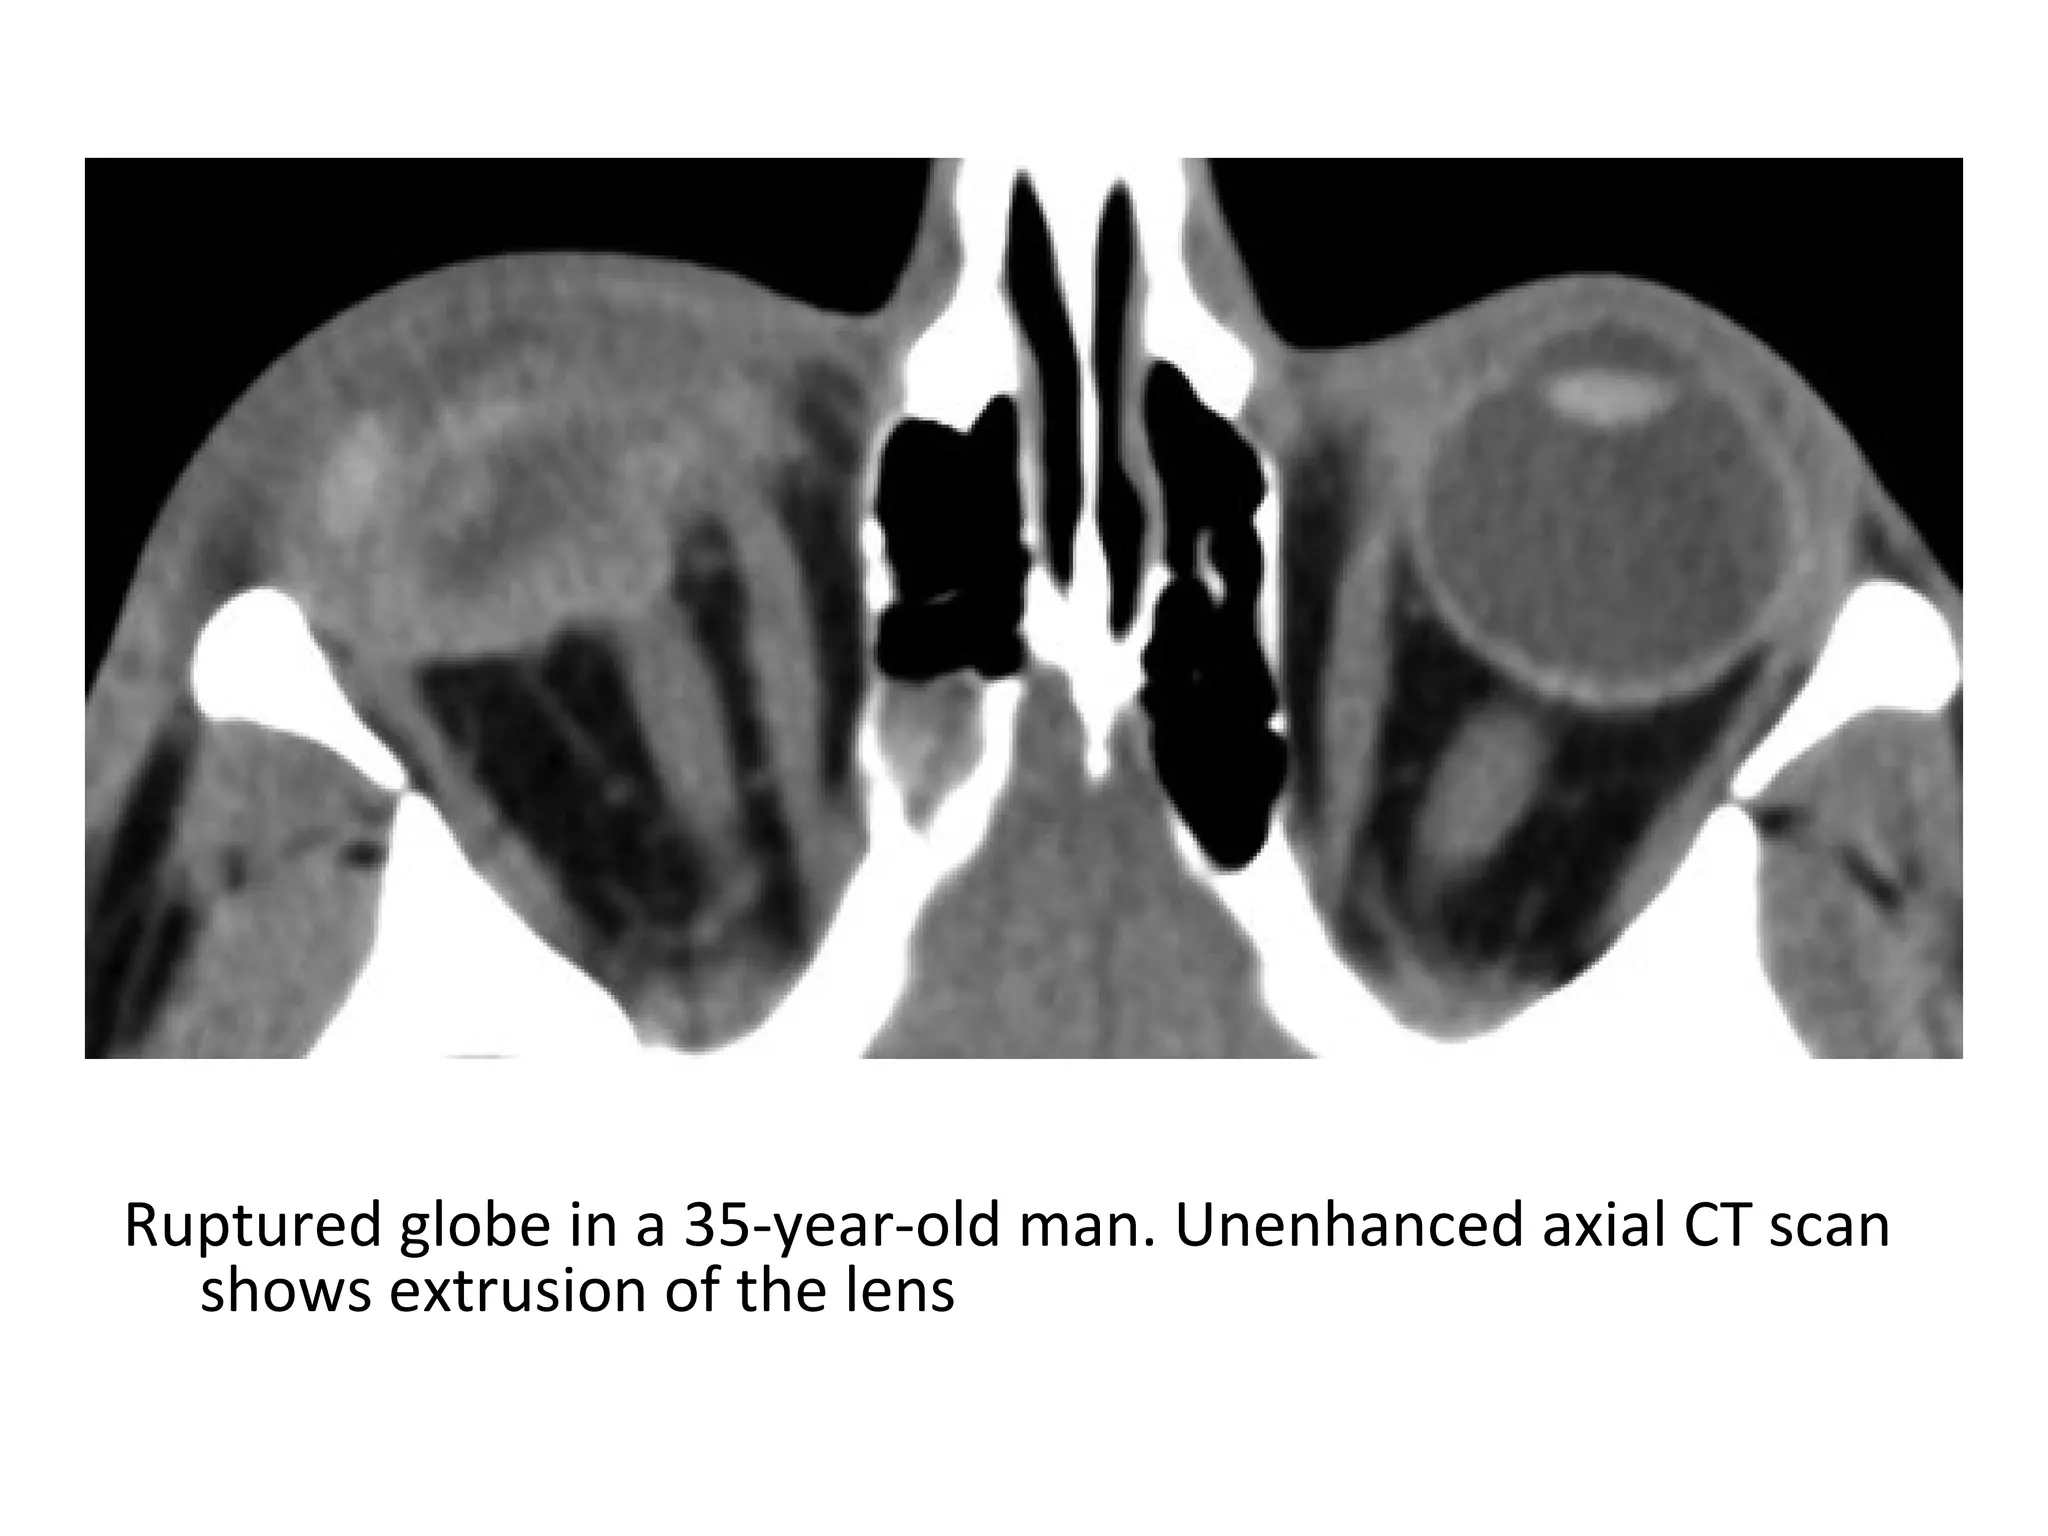

Ruptured globe in a 35-year-old man. Unenhanced axial CT scan

shows extrusion of the lens